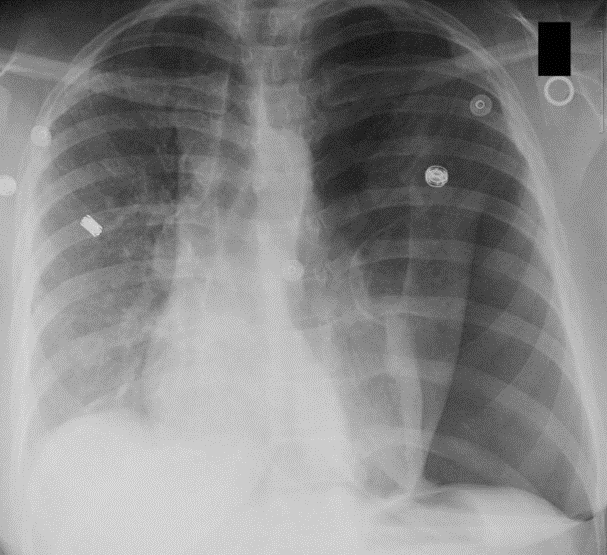

Spontaneous Pneumothorax

(well demarcated line, right side is super black bc no lung tissue there)